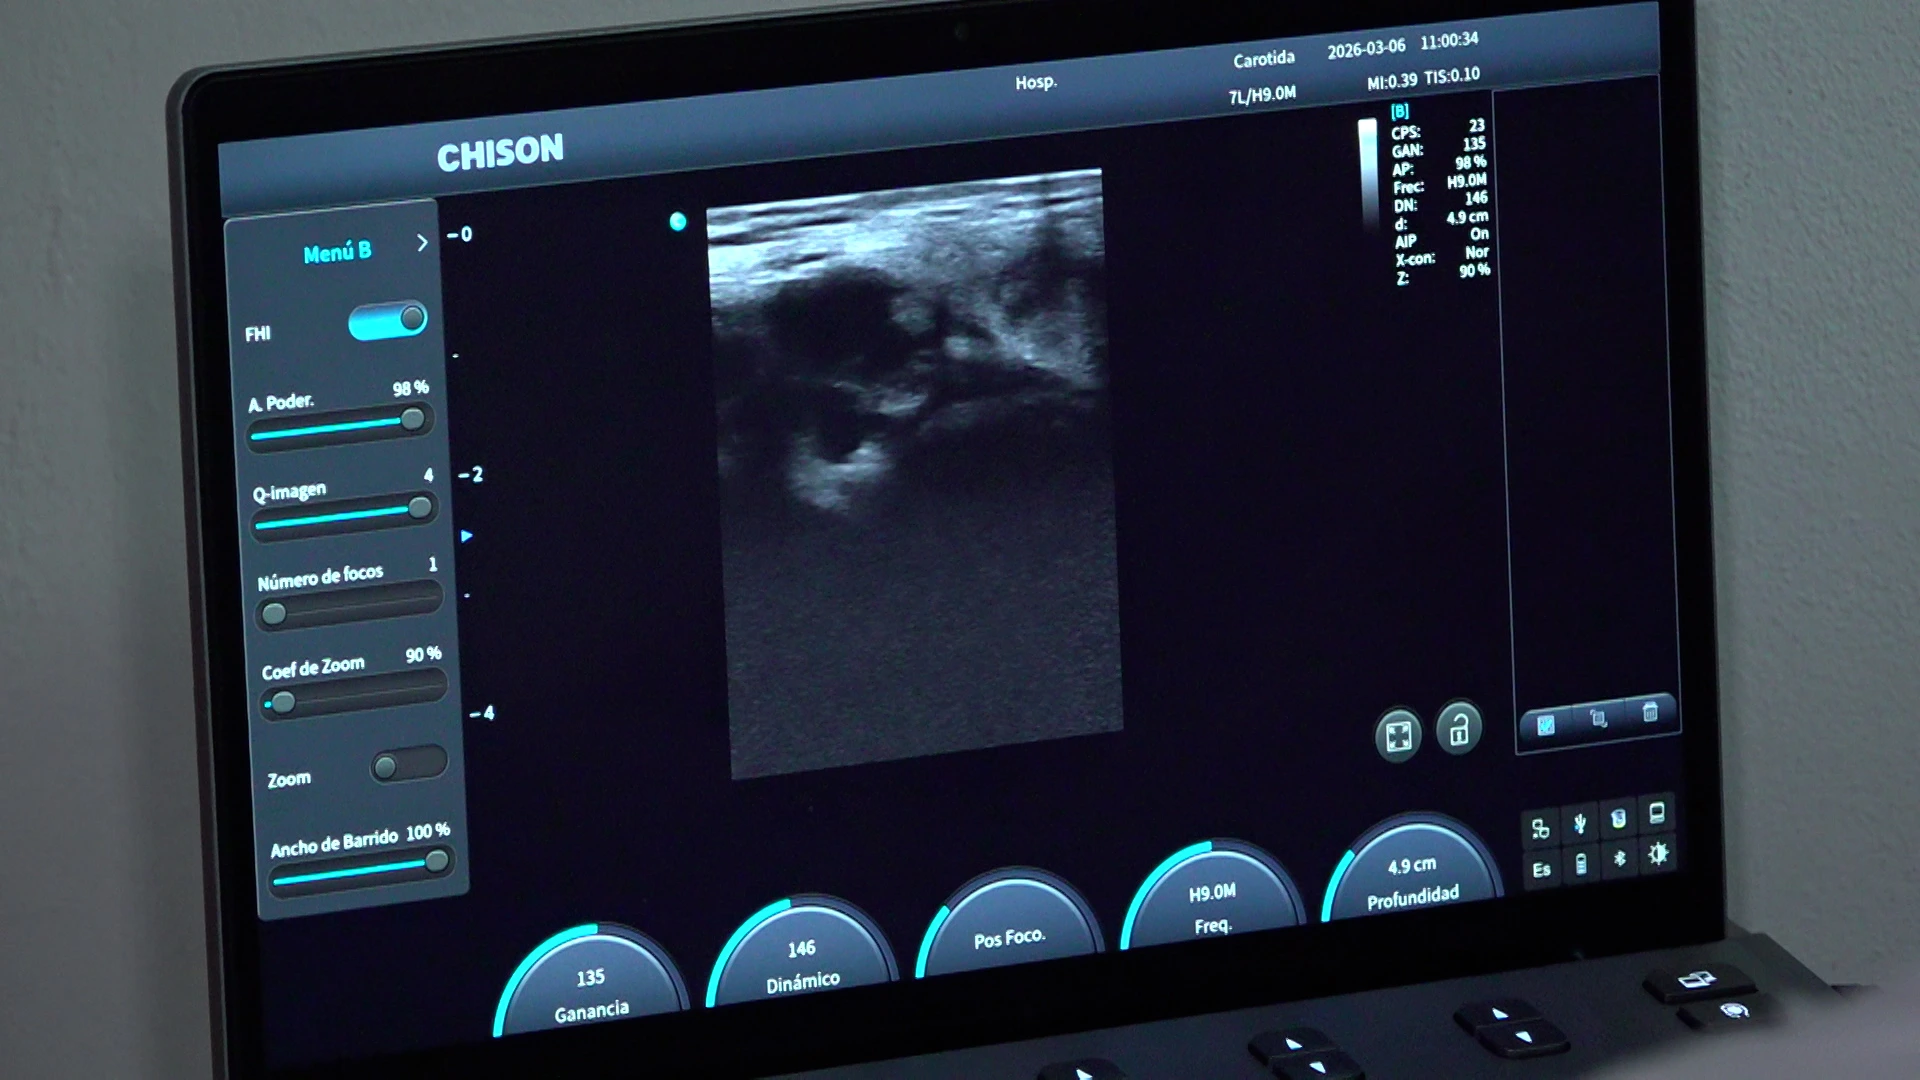

“Una de las estrategias está enfocada en el diagnóstico oportuno y para esto estamos realizando la campaña Nora Astorga , en la cual hacemos mamografías, ultrasonidos, toma de biopsias de mama, con resultados dados al paciente en menos de una semana”, indicó.

La doctora Cruz resaltó que, si el resultado sale positivo a cáncer, se apoyan con la red para localizar al paciente, hacerle estudios como valoraciones cardiovasculares, ultrasonidos de abdomen, estudio de huesos, para posteriormente dar un tratamiento.